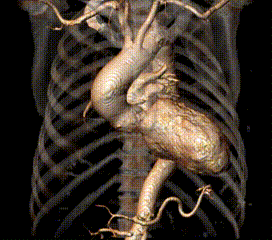

CT显示Type0型二叶瓣,瓣叶中重度钙化伴增厚粘连,存在人工瓣膜形变、瓣环撕裂及根部损伤风险;大瓣环、钙化分布不均匀及瓣口形态限制,人工瓣膜锚定难度较高,瓣周漏风险高,存在瓣中瓣风险。严重横位心(75°),输送系统过弓、跨瓣难度较高。

对于此例病人,严重横位心75°,器械需要出色的柔顺性与通过性在手术过程不损伤血管;瓣膜需要良好的径向支撑力,避免出现下滑的风险。在武汉大学中南医院心脏中心结构性心脏病团队通力协作下,顺利完成此例高难度手术,术中评估TaurusElite AV29mm瓣膜锚定良好,术后造影结果显示瓣膜形态、位置良好,仅少量瓣周漏。手术即刻超声测量,主动脉瓣工作良好,瓣口流速从术前的5.2m/s改善为1.8m/s,跨瓣压差从术前的106mmHg改善为8mmHg。